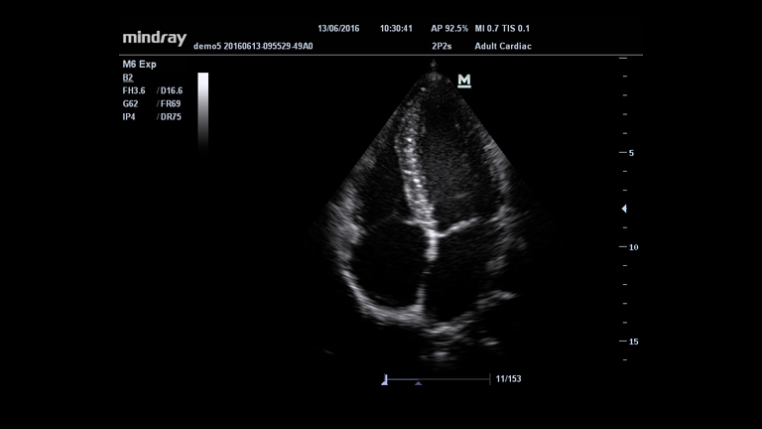

Informacje og├│lne

Multi-Beam Formation (Tworzenie wielu wi?zek)

iClear?

iBeam? (obrazowanie krzy?owe)